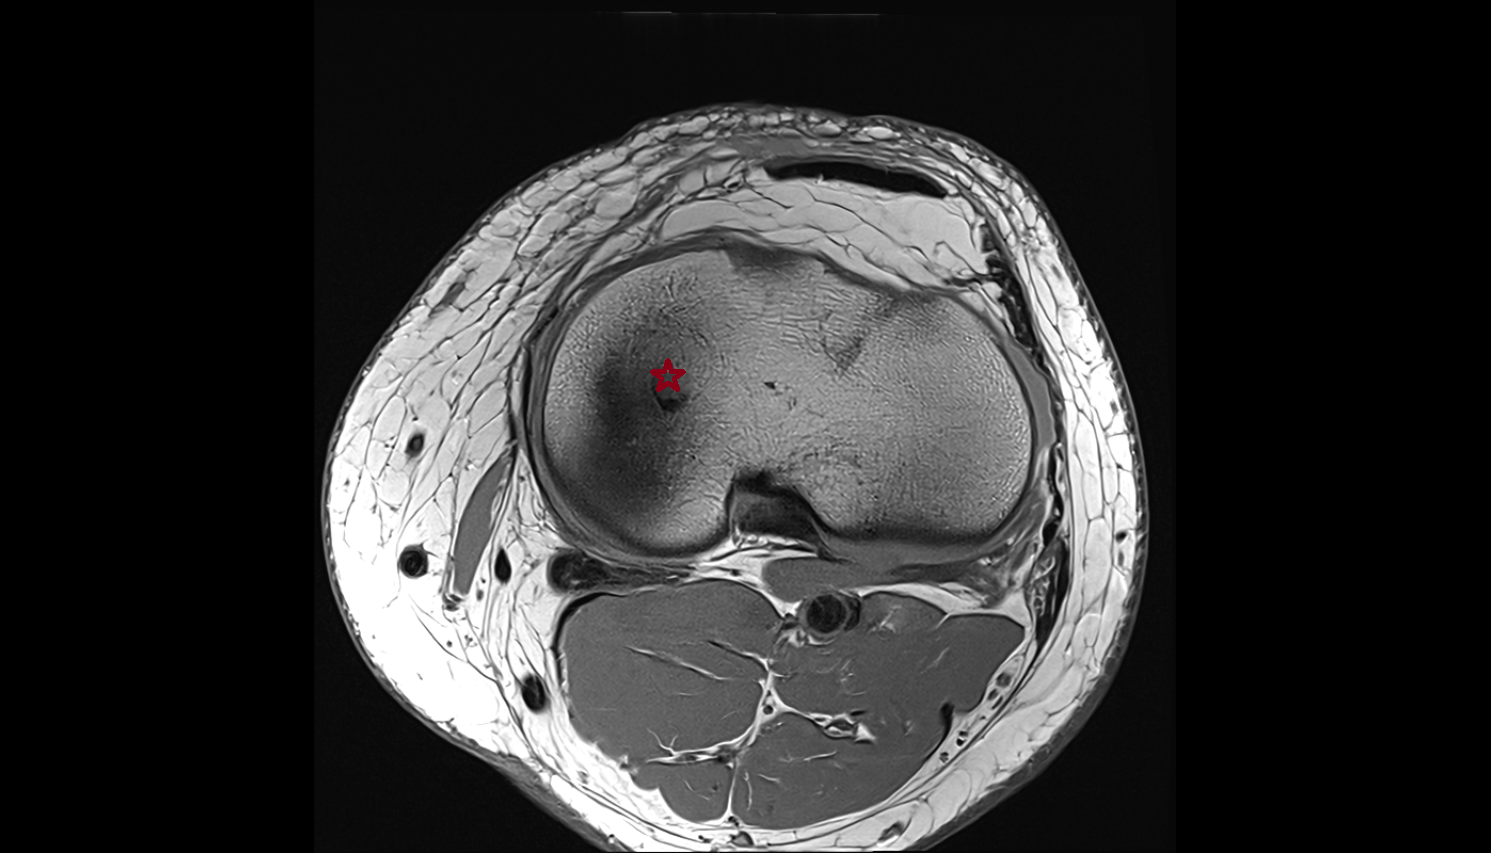

- Patella

- Patellar articular cartilage

- Infrapatellar fat pad

- Suprapatellar fat pad

- Prefemoral fat pad

- Trochlear groove